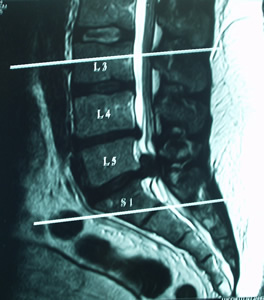

Hernia Discal cervical / Hernia Discal Lumbar

La hernia discal es la invasión del disco intervertebral hacia el canal medular, y puede producir la compresión de la médula y de los nervios sensitivo y/o motor. Es una patología frecuente en la columna cervical y lumbar y puede ser sintomática o asintomática. Los síntomas varían de acuerdo a la región; el dolor local, el dolor irradiado, las parestesias (hormigueos) en el miembro superior o inferior, los cambios repentinos en el color y sudoración de la piel, impotencia motriz, debilidad muscular y atrofia, falta de sensibilidad y contracturas son síntomas comunes a las dos regiones. Los mareos, náuseas, acufenos, migrañas y dolores punzantes en la base del cráneo son habituales en la zona cervical. Los trastornos esfinterianos, la escoliosis lumbar antalgica y el dolor ciático son propios en la hernia discal lumbar.

El tratamiento de la hernia discal en RPG consiste en lograr la convivencia entre la estructura (la columna vertebral, los ligamentos, cápsulas, los músculos) y el disco herniado, abriendo el espacio en el segmento vertebral involucrado. El abordaje será a través de: